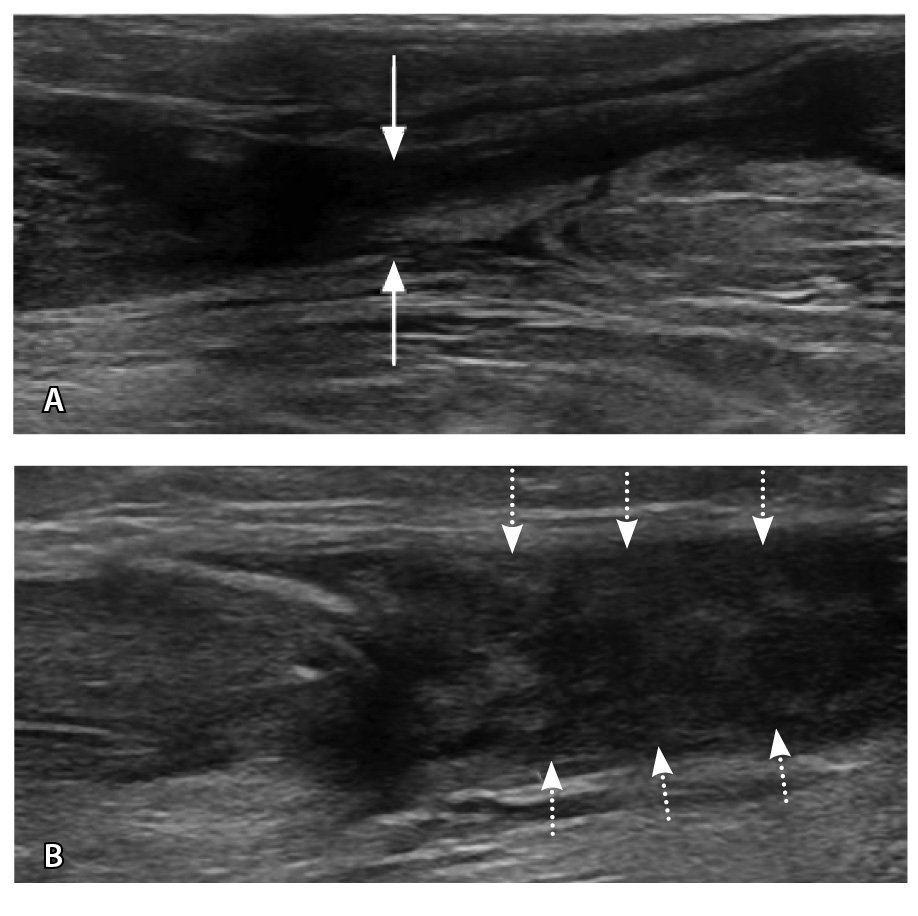

По данным N. El-Liethy и H. Kamal чувствительность сонографии в диагностике повреждения ахиллова сухожилия и сухожилия задней большеберцовой мышцы составила 100%, при этом в последующем результаты подтвердились при помощи МРТ. Существует мнение, что с помощью УЗИ удается классифицировать повреждения ахиллова сухожилия (рис. 6) аналогично МРТ в отношении тендинопатии, частичного повреждения и полного разрыва [58].

Рис. 6. Ультразвуковая диагностика голеностопного сустава: А – неполнослойный разрыв ахиллова сухожилия в области мышечно-сухожильного перехода (стрелки); Б – дефект 90% волокон, заполнен геморрагическим содержимым (пунктирные стрелки). Диастаз волокон, гематома